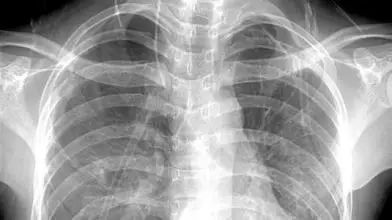

X光:像把面包压扁了看

X光会穿过人体,遇到被遮挡的部位,底片上不会曝光,洗片后这个部位就是白色的。

就像一片面包或一块棉花,看不到里面的纤维纹理,但用手压瘪了会清晰一些。X光最大缺点是受制于深浅组织的影像相互重叠和隐藏,有时需要多次多角度拍摄X光片。

3、胸部——粗看X光片,细看CT

X光胸片可粗略检查心脏、主动脉、肺、胸膜、肋骨等,可以检查有无肺纹理增多、肺部钙化点、主动脉结钙化等。

胸部CT检查显示出的结构更清晰,对胸部病变检出敏感性和显示病变的准确性均优于常规X光胸片,特别是对于早期肺癌确诊有决定性意义。但是,CT检查的辐射剂量高于X光。核磁对于肺部疾病的诊断,应用非常有限。